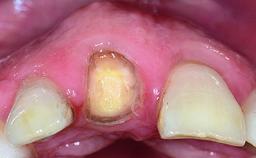

A 32-year-old female Caucasian patient with a compromised maxillary right central incisor was referred to us by a general dentist. Her chief complaints were discomfort and mobility of tooth 11 with unsatisfactory esthetics due to discoloration. The patient reported a previous trauma, some years earlier, as the origin of pathology on the afflicted tooth. Anamnesis was negative for any other dental or periodontal pathology in the remaining dentition. The patient did not take any medication and reported to be a light smoker (5–10 cigs/day). She had high esthetic expectations of her treatment. The extraoral examination revealed a high smile line with full exposure of her maxillary teeth and surrounding soft tissue in the area between the second premolars.

Periodontal Phenotype Low-scalloped, thick Medium-scalloped, medium-thick High-scalloped, thin

Soft Tissue Anatomy Intact Defective

Soft Tissue Contour and Volume Slightly compromised